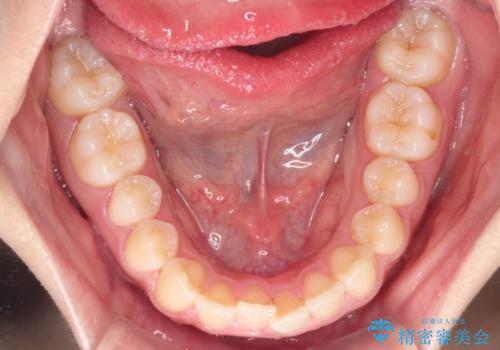

- 患者様は、**下の前歯のがたつき(叢生)**を気にされて来院されました。

下の前歯のがたつきは解消され、滑らかなアーチ状の歯並びとなりました。